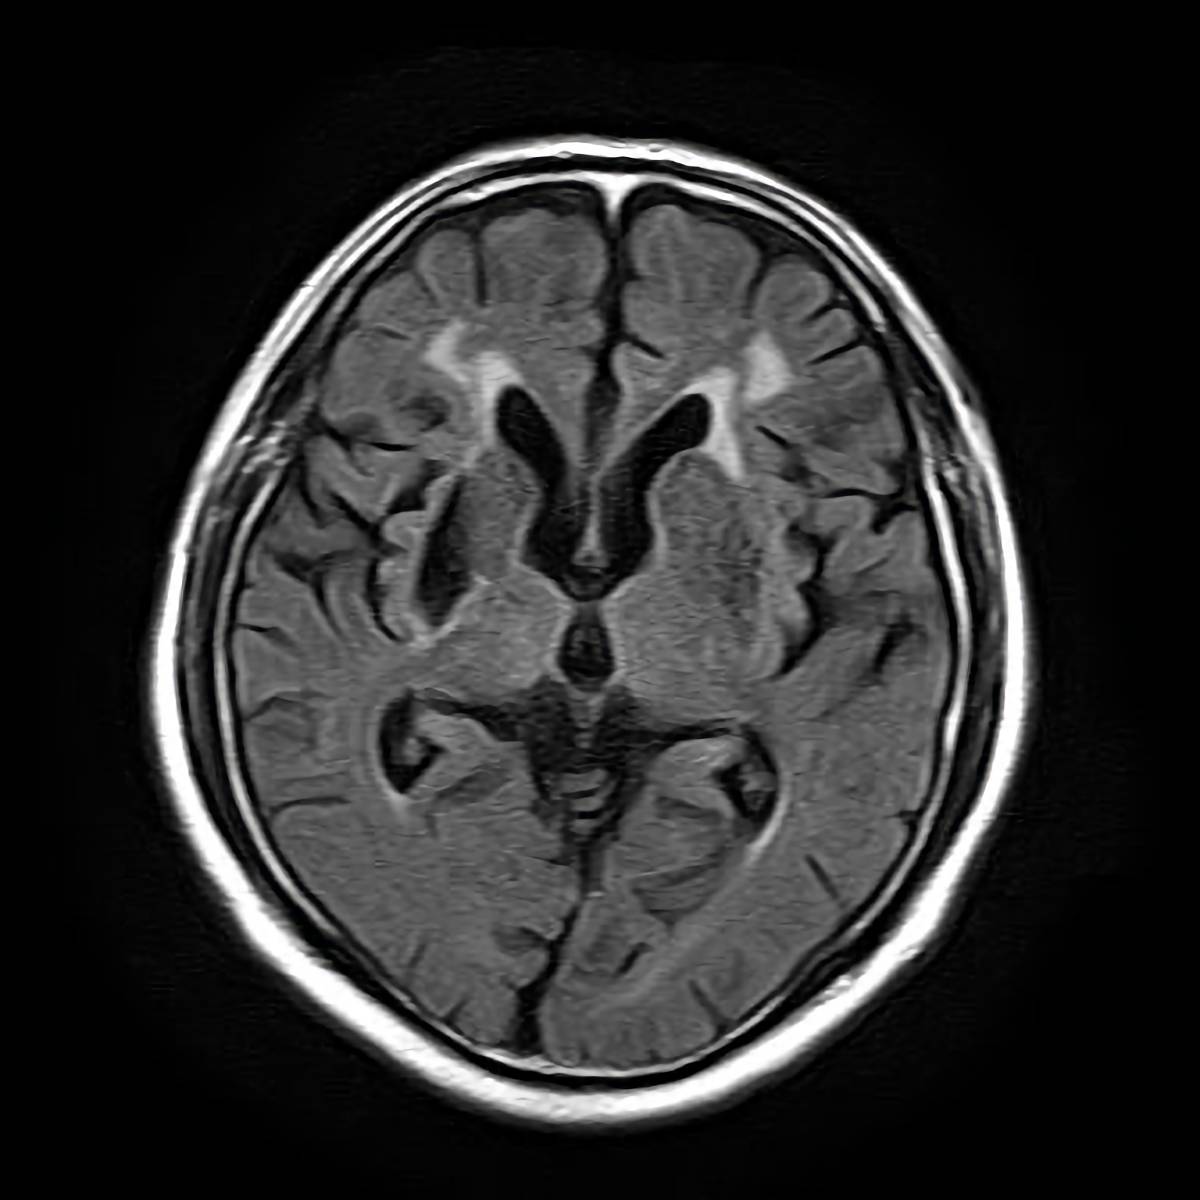

FLAIR